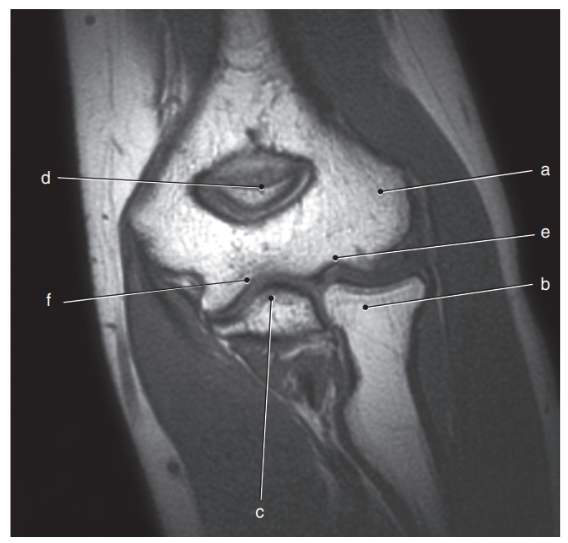

What is letter a ?

Lateral epicondyle

What is letter e ?

Olecranon process

What is letter c ?

Coronoid process

What is letter a?

Biceps brachii tendon

What is letter f ?

Acromion process